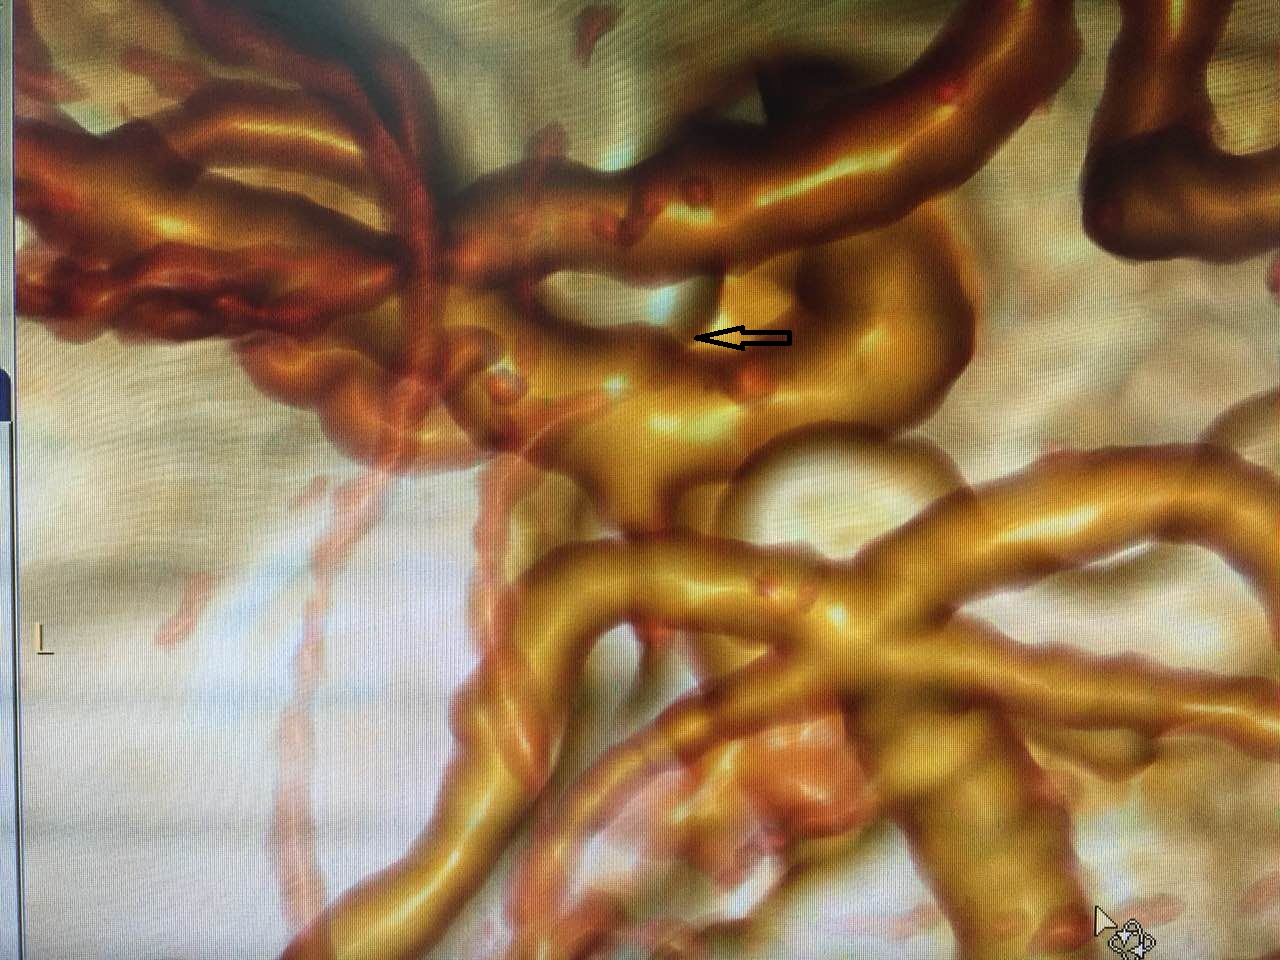

术前CTA

术前DSA

这位40多岁身强力壮的盛师傅到底是得了什么病呢,他既没有高血压也没有心脏病,为何情况会如此凶险呢?原来,脑血管造影结果显示,极为罕见的血泡样动脉瘤让这位盛师傅给赶上了。大脑动脉瘤估计大家并不陌生,也知道这是非常凶险的疾病,一旦破裂凶多吉少,而盛师傅的血泡样动脉瘤更是动脉瘤中的“轰炸机”!

血泡样动脉瘤起自颈内动脉床突上段前壁非分叉部,该类型的动脉瘤实际是假性动脉瘤,特点是瘤体为血管壁外膜,无瘤颈,极为菲薄透明,在对其手术的过程中及术后都极易发生破裂出血,死亡率极高,治疗也非常困难,对术者的专业素质和心理素质都有着极高的要求。